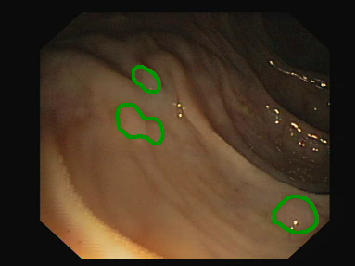

Figure 1: Polyp visual aspects have a wide variety in terms of shape and color. Four different polyps sampled from the different databases considered in this work: (a) Kvasir-Seg [19], (b) CVC-ClinicDB [5], (c) CVC-ColonDB [4], (d) ETIS [29].

The large bowel within the human gastrointestinal tract can be affected by different diseases, among which, Colorectal Cancer (CRC) is particularly concerning. CRC represents the second most common cancer type in women and third most common for men [15]. Gastro-intestinal polyps are known precursors of this type of cancer [34], being present in almost half of the patients over 50 undergoing screening colonoscopies [31]. This kind of lesions show a wide range of shapes and visual appearances, as shown in Fig. 1, turning its identification and segmentation into a challenging problem.